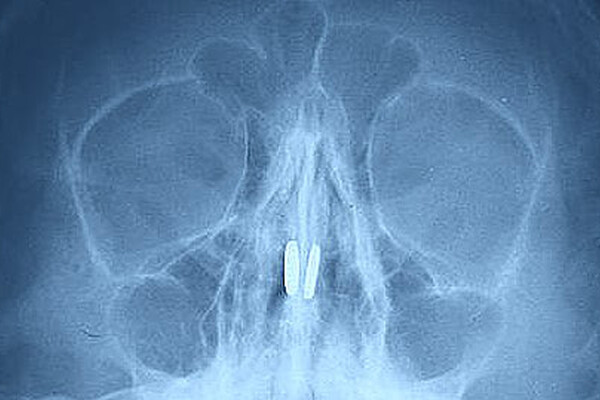

Маленький пациент был доставлен в медицинское учреждение с жалобами на боль в носу и проблемы с дыханием. В ходе обследования в носовых пазухах были обнаружены магниты от игрушки, которые притянулись друг к другу через носовую перегородку.

Инородные тела извлекли специальным крючком, серьезных повреждений мальчик не получил.